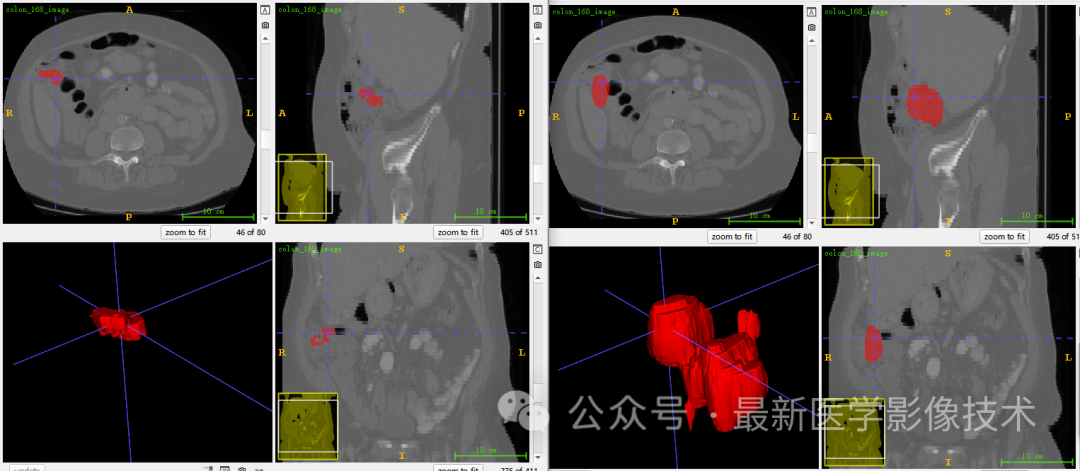

5、验证集分割结果

左图是金标准结果,右图是预测结果。